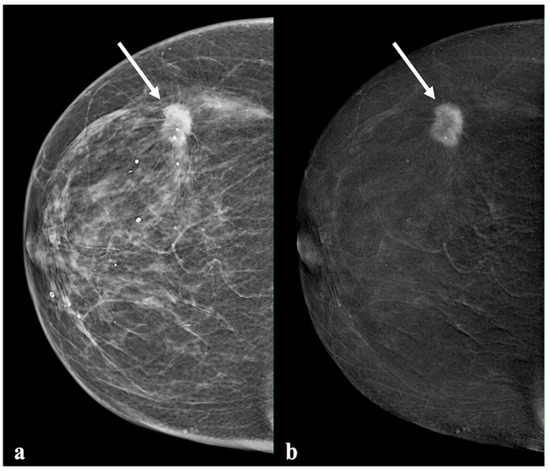

2.2. Contrast-Enhanced Mammography

2.3. Image Analysis